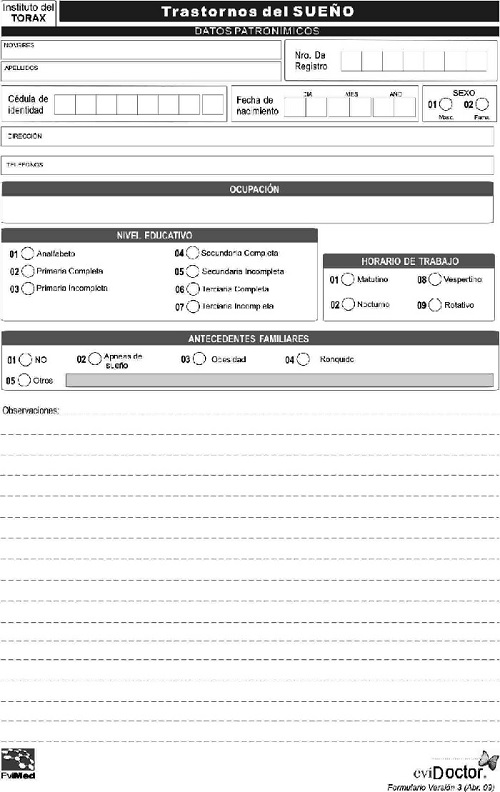

Se revisaron los registros de 3109 pacientes, (2279 del sistema mutual y 830 del Hospital de Clínicas), del período comprendido entre 1990 y 2014. En un subgrupo de pacientes con apneas del sueño (n = 447), se aplicó una historia clínica electrónica (HCE), desarrollada para este fin por Evimed (www.evimed.net, Apéndice 1), que permitió el relevamiento de casos desde 2010 a 2014. Este conjunto fue usado para relacionar los resultados de la anamnesis y el examen físico con datos fisiológicos. Para la evaluación cuantitativa de los síntomas y el impacto de la calidad del sueño en múltiples actividades de la vida diaria se aplicaron la escala de somnolencia de Epworth5 y el cuestionario de resultados funcionales del sueño FOSQ6.

Las modalidades de estudios del sueño utilizadas7)(8)(9)(10)(11 incluyeron: polisomnografía atendida por técnico en laboratorio del sueño (nivel 1) en sus modalidades de noche completa y noche dividida, en 2891 casos (93%). En el sistema mutual exclusivamente, a partir del año 2012 se utilizaron polisomnografía portátil del sueño (nivel 2) ó poligrafía respiratoria durante el sueño (nivel 3) en 183 casos (5.9%) y oximetría de pulso durante el sueño (nivel 4) en 35 casos (1.1%).

La polisomnografía incluyó registro simultáneo de: video con luz infrarroja, posición corporal, electroencefalograma, electrooculograma, electromiograma mentoniano y de miembros, micrófono en el cuello, electrocardiograma, flujo aéreo nasal y bucal (termistor), flujo nasal (presión), movimientos respiratorios abdominales y torácicos (sensor piezoeléctrico) y saturación de oxígeno del pulso. La estadificación del sueño se realizó en forma manual mediante lectura del registro diferida, siguiendo criterios estandarizados de Rechtschaffen y Kales12. A partir de 2007 se usó la actualización de la estadificación de la AASM13. Para la clasificación de los diagnósticos se utilizó la Clasificación Internacional de Trastornos del Sueño14.

Los instrumentos utilizados fueron: polígrafos Grass 49, ATI Delphos, Akonic, Copumedics Somte y Apnea Link; oxímetros Criticare 504 y NonIn.